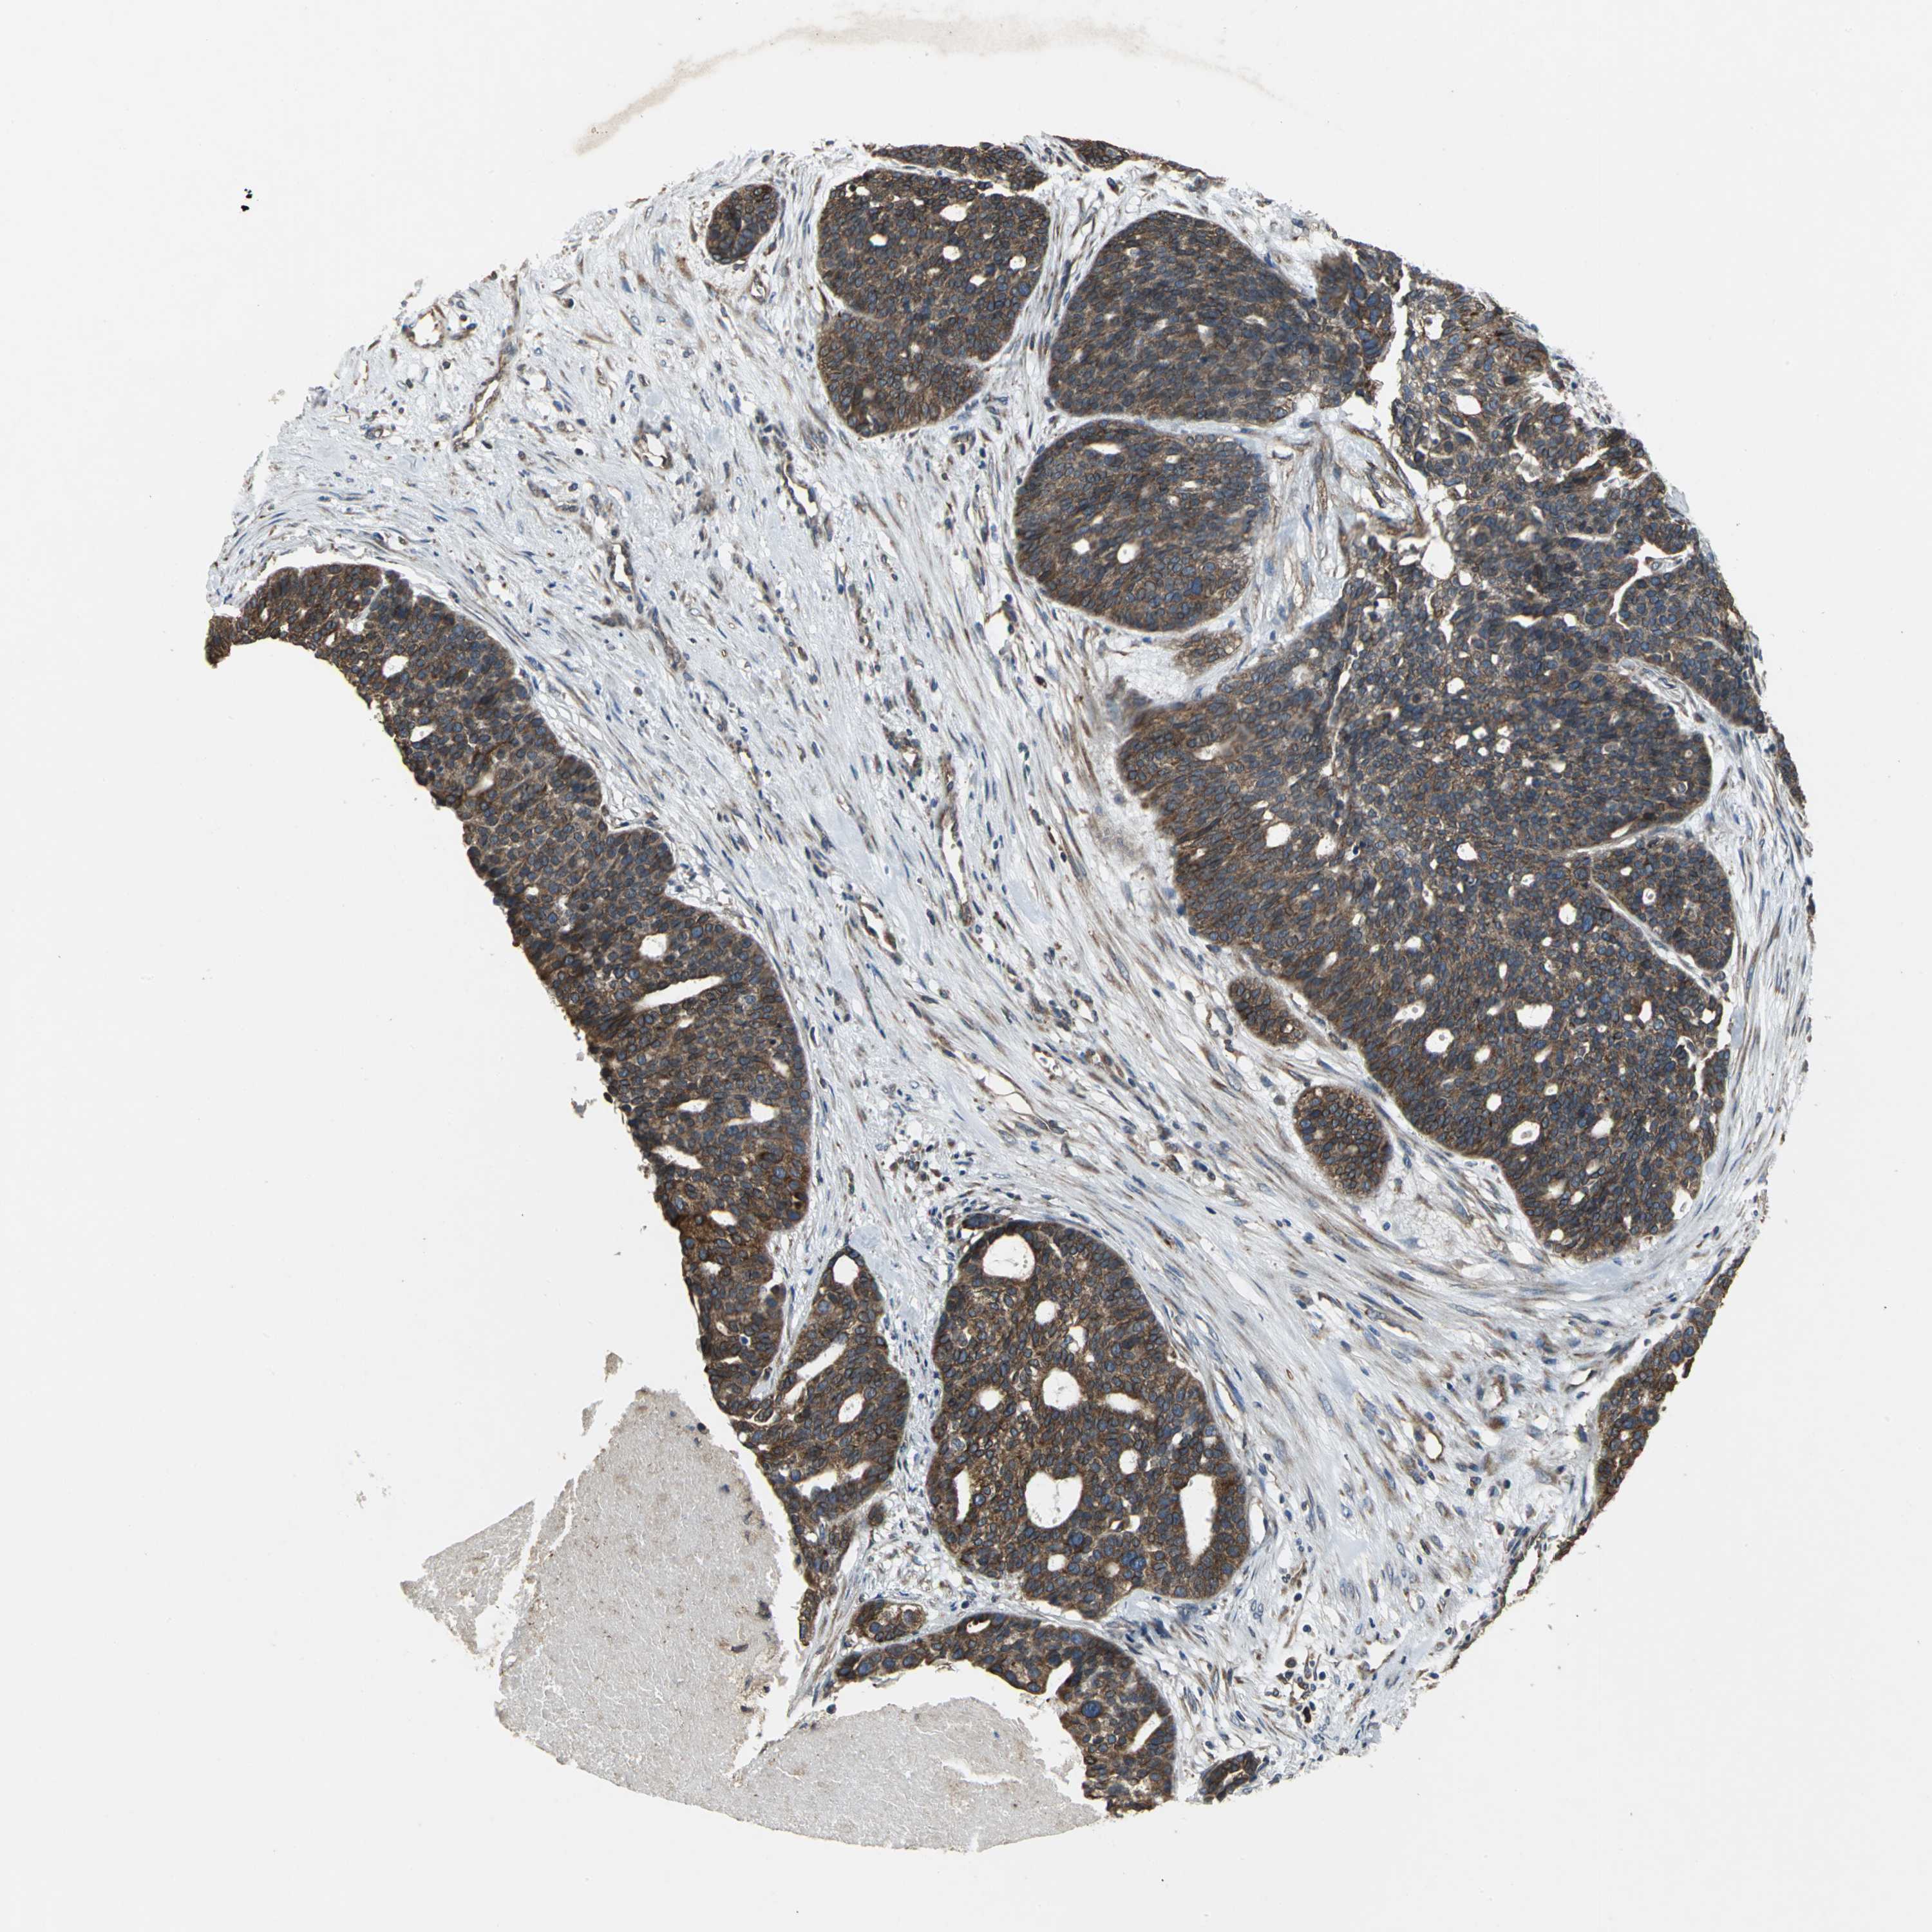

OVARIAN CANCER - Protein expressioni

A mouse-over function shows sample information and annotation data. Click on an image to view it in a full screen mode. Samples can be filtered based on level of antibody staining by selecting one or several of the following categories: high, medium, low and not detected. The assay and annotation is described here.

Note that samples used for immunohistochemistry by the Human Protein Atlas do not correspond to samples in the TCGA dataset.

Antibody stainingi

Antibody staining in the annotated cell types in the current human tissue is reported as not detected, low, medium, or high, based on conventional immunohistochemistry profiling in selected tissues. This score is based on the combination of the staining intensity and fraction of stained cells.

Each image is clickable and will lead to virtual microscopy that enables deeper exploration of all samples and also displays staining intensity scores, fraction scores and subcellular localization as well as patient and tissue information for each sample.

Antibody HPA005480

Cystadenocarcinoma, serous, NOS

Carcinoma, endometroid

Carcinoma, NOS

Cystadenocarcinoma, mucinous, NOS